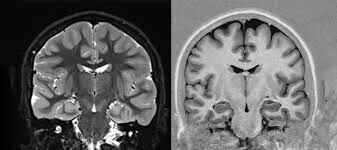

Beyin küçülmesi, baş dönmesi, denge kaybı, konuşma bozukluğu, unutkanlık veya kişilik değişiklikleriyle fark edilebilir. Erken tanı nöroloji uzmanları tarafından yapılır; MR görüntüleme, kan testleri ve nöropsikolojik değerlendirmeler sürece yardımcı olur. İlaç tedavisi tamamen durdurmasa da süreci yavaşlatabilir; anti-dementif ilaçlar, kolinesteraz inhibitörleri ve B12 takviyeleri doktor kontrolünde kullanılabilir.